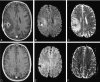

Fig 1.

Patient 1. A 40-year-old man with mild ataxia and homonymous hemianopia. CRP level was initially 0.5 mg/dL and did not change in the clinical course. WBC count was mildly increased initially and decreased soon after surgical drainage. DW images were well correlated with conventional MR images, showing no re-accumulation of pus. A, Axial contrast-enhanced T1-weighted image shows a ring-enhancing lesion in the left occipital region, with perifocal edema. B and C, Trace DW images show a hyperintense lesion and a low ADC indicating restricted diffusion. Clinical and imaging findings were consistent with brain abscess. D–F, Four days after surgical drainage, contrast-enhanced T1-weighted image (D) shows that the lesion is diminished, with predominantly low signal intensity on a DW image (E) and a high ADC on ADC map (F); these finding suggest clear fluid in the abscess cavity.